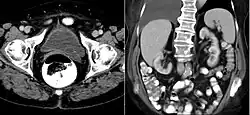

CT scan showing a ureterocele associated with a duplicated collection system of the left kidney.